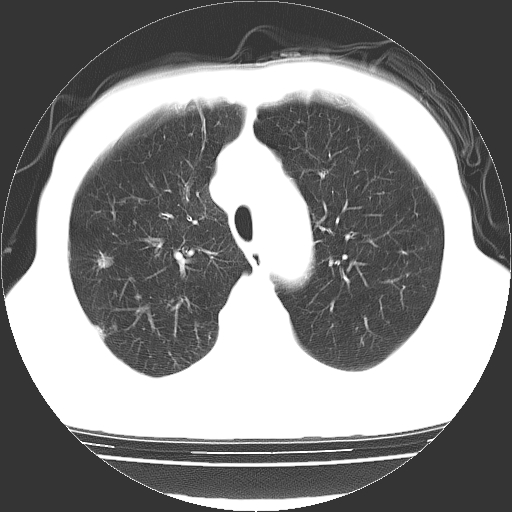

以下是引用hhcckk在2009-1-1 15:38:00的发言:[br]左下肺少许絮状模糊影--考虑感染[br]两肺散在小点状密度增高影--结合病史考虑矽肺?[br]气管壁钙化--可能由于老年退变性引起的